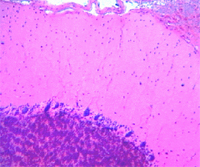

浦肯野細胞(Purkinje cell)是從小腦皮質發出的唯一能夠傳出衝動的神經元。浦肯野細胞軸突穿過顆粒層和白質到達深部小腦核團,浦肯野細胞在運動協調中起著重要的作用。 許多疾病和物質都可以造成浦肯野細胞損傷,浦肯野細胞損傷後可以導致共濟失調。並且可以引起TNF-α和TGF-β2表達的異常。

研究人員著眼於小腦的一種神經細胞“浦肯野細胞”。在胎兒大腦的蛋白質中加入胰島素培育ES細胞,8天后全體的約8成均轉變為小腦幹細胞,再過5天又有3成以上變為浦肯野細胞。將該浦肯野細胞移植入老鼠胎兒體內,成功與一部分小腦實現結合,形成發揮作用的神經迴路。